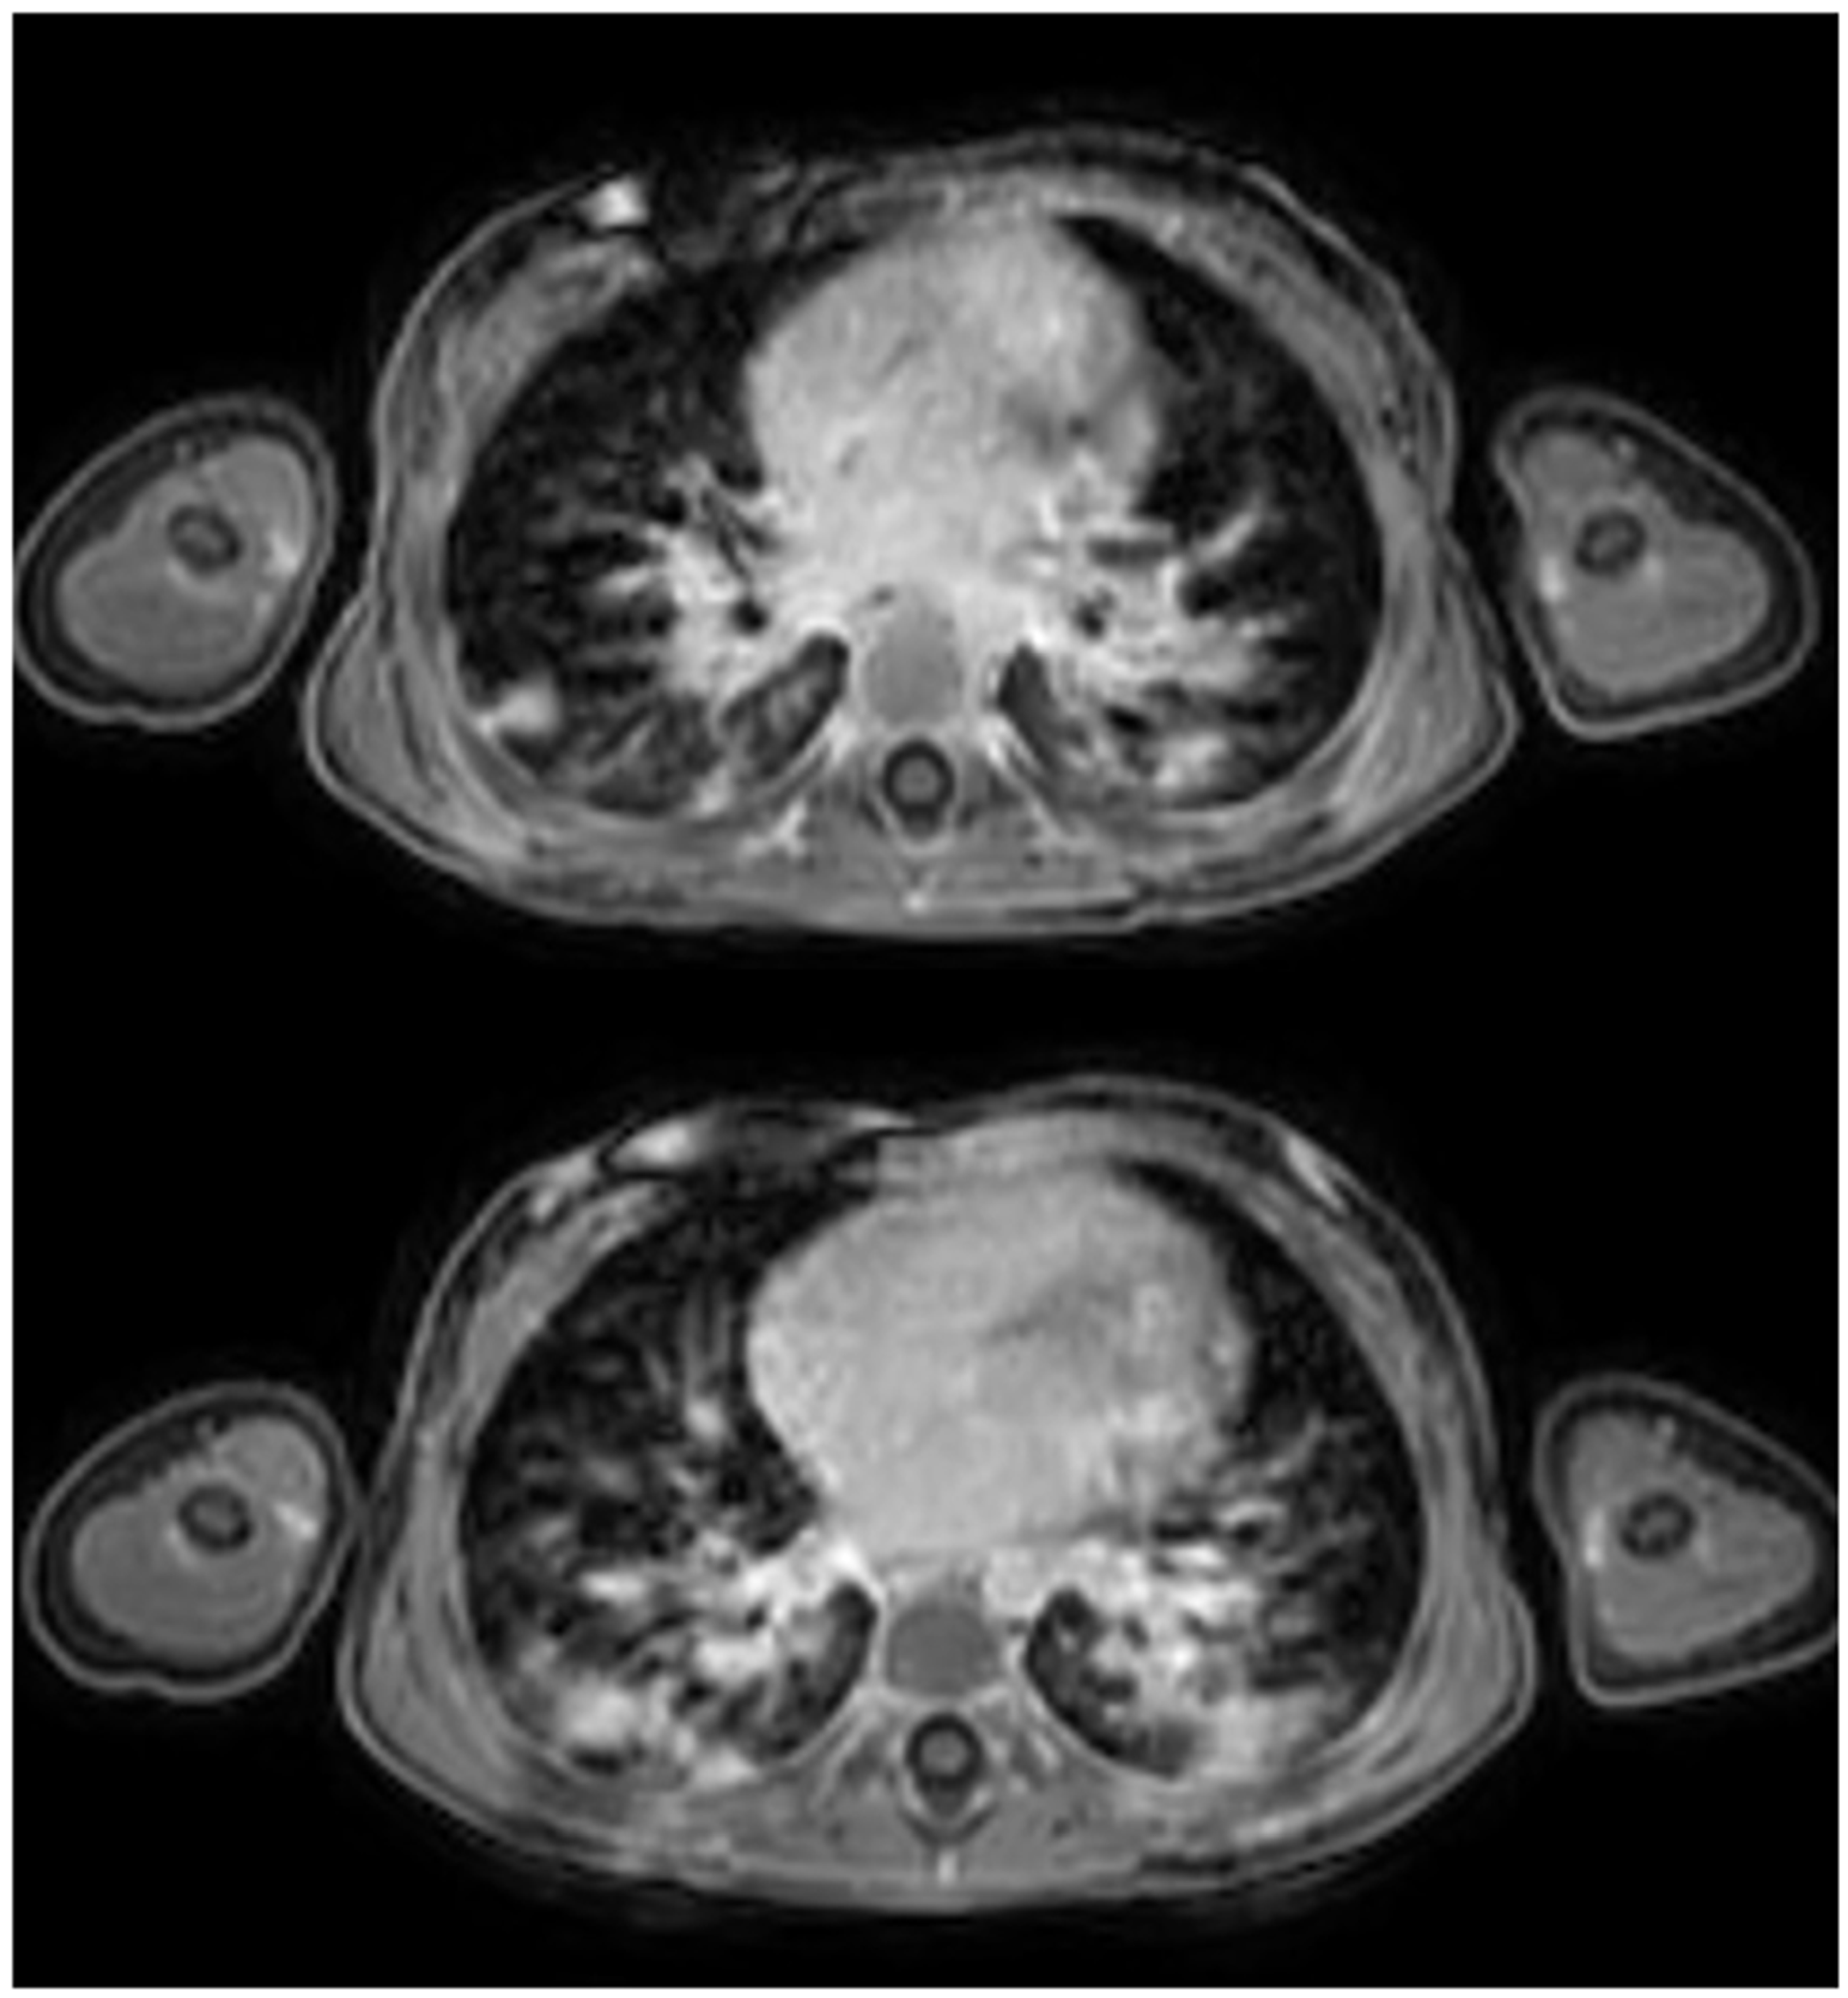

- Tischendorf, P.; Kunnemann, M.D.; Krahling, T.; Lange, J.H.; Heindel, W.; Beck, L. Thoracic MRI in Pediatric Oncology: Feasibility and Image Quality of Post-Contrast Free-Breathing Radial 3D T1 Weighted Imaging. Biomedicines 2025, 13, 2302. [Google Scholar] [CrossRef]